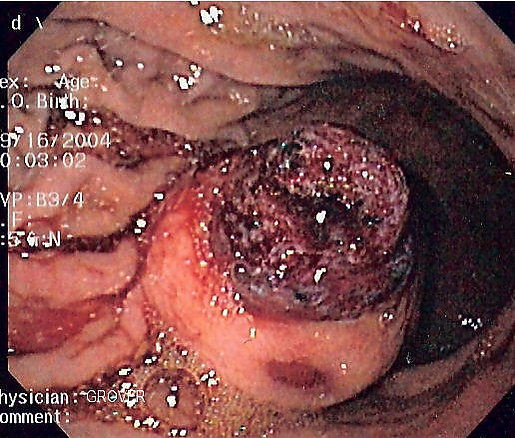

Биоптат исследуется под микроскопом для выявления особенностей ГИСО (веретеноклеточный вариант — 70—80 %, эпителиодный — 20—30 %). Опухоли небольших размеров обычно могут быть ограничены мышечным слоем стенки органа. Крупные опухоли обычно растут, преимущественно кнаружи, из стенки органа, пока их объём не превысит их кровоснабжение, после чего в толще опухоли развивается некротическая полость, которая может в конечном счёте сформировать соустье с полостью органа.

Крупные ГИСО

По мере роста опухоли, она может проецироваться снаружи от органа (экзофитный рост) и/или в просвете органа (интралюминальный рост); чаще всего ГИСО растут экзофитно, таким образом большая часть опухоли располагается в проекции брюшной полости. Если увеличение объёма опухоли опережает рост её кровоснабжения, опухоль может некротизироваться в толще, с формированием центральной зоны жидкостной плотности и кавитацией, что может приводить к изъязвлению и формированию соустья с полостью органа. В этом случае исследование с бариевой взвесью может демонстрировать газ, уровни газ/жидкость или депонирование контрастного препарата в этих областях.[17][18] При КТ с контрастным усилением крупные ГИСО выглядят негомогенно, в связи с неоднородностью структуры опухоли, обусловленной участками некроза, кровоизлияниями и полостями, что радиологически проявляется контрастированием опухоли преимущественно по периферии.[16]